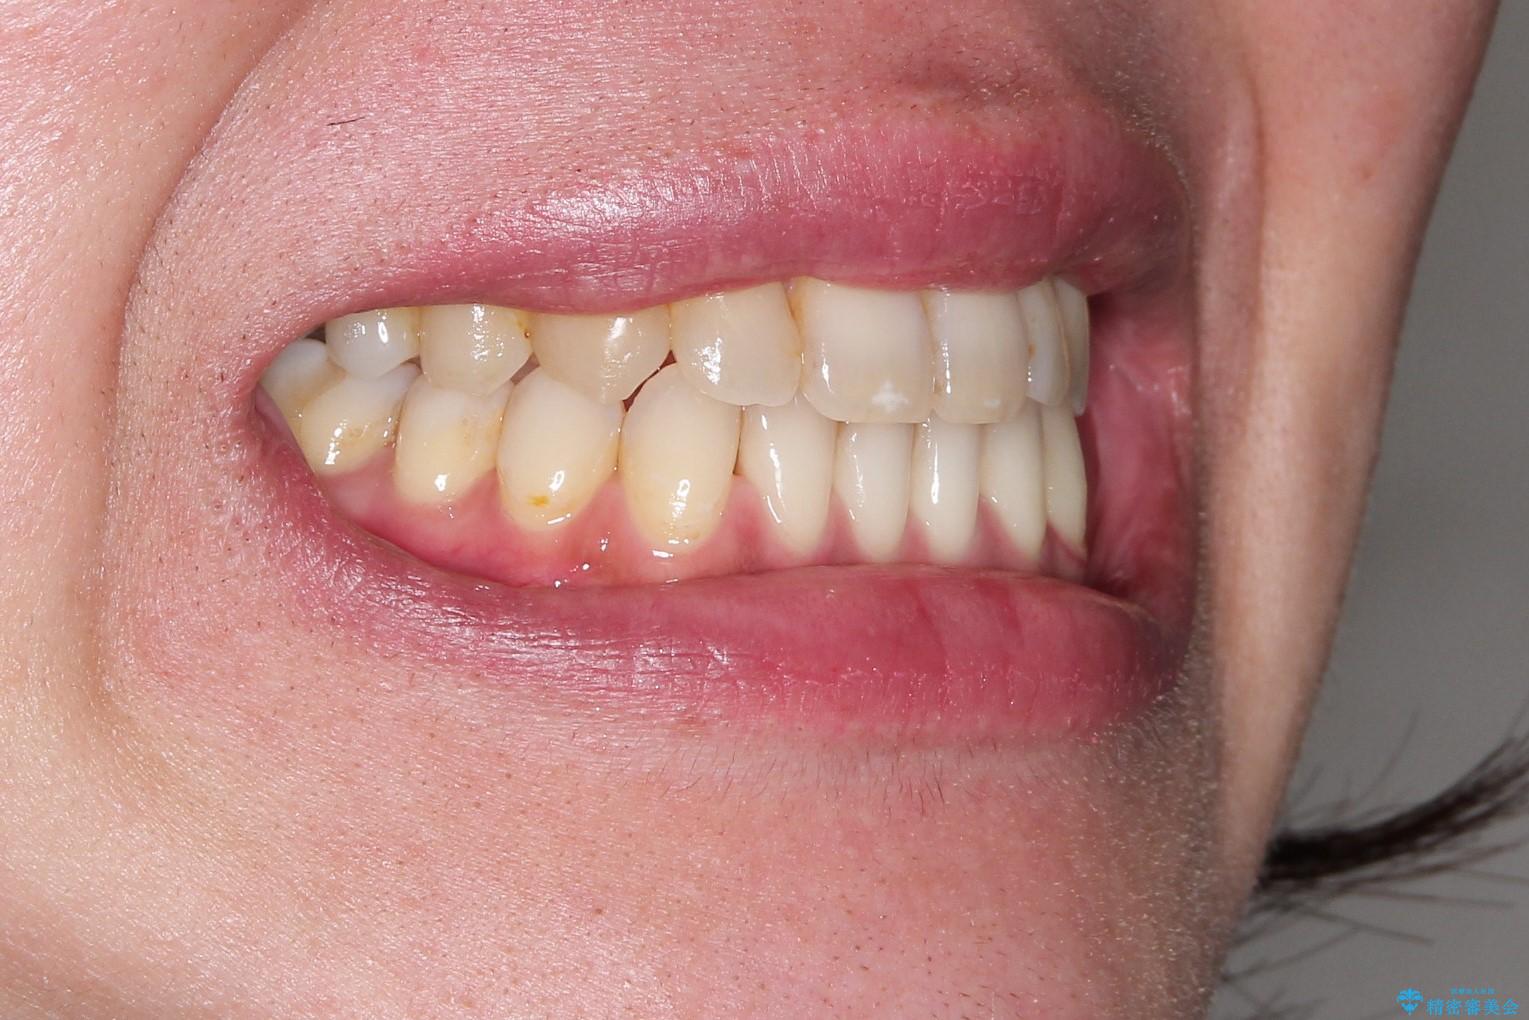

Invisalign インビザライン によるガタつき、受け口傾向の改善

奥歯の位置関係の修正は難儀することが多いマウスピース矯正ですが、割とスムーズに奥歯の位置関係の修正をすることができました。

クロスバイトもきれいになり、きれいな歯並びとなりました。